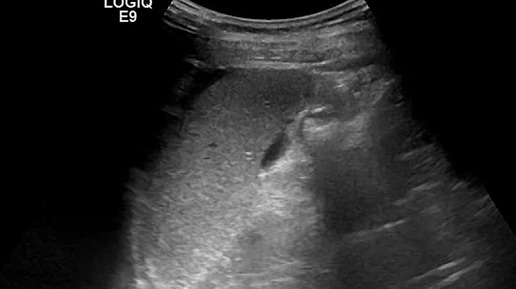

Видео к статье: "Свободная жидкость в брюшной полости"https://dzen.ru/a/Z-1KdOK-KyrjRiGF

Ультразвуковые находки от врача УЗД Зорина Я.П.